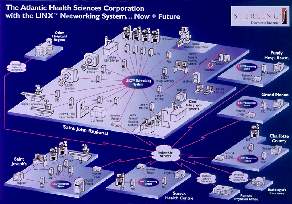

En esta region vamos a conectar seis hospitales mediante una WAN ATM de 100

y 10 Megabits, Linux no tiene nada que ver en esta red, el solo actua sobre

ella, pero permite resaltar la importancia dada al tema radiologico.

La cabeza de todo el sistema se situa en St. John, este tiene dos

archivadores :

- 1 Pentium Pro a 200Mhz

- 112G de disco duro

- 1 robot DAT con 200G en cintas

- 1 tarjeta red 10Mb

- 1 tarjeta red 100Mb

Luego otro archivador de mismas caracteristicas pero con "solo" 27G en St.

Joseph

En una primera fase la red la conformaran seis hospitales, añadiendose dos

mas en la segunda fase del proyecto, en esta primera fase se van a conectar:

- 4 estaciones X11 con doble pantalla para diagnostico en los propios

hospitales

- 12 estaciones W95 para las consultas en los diversos hospitales

- 17 estaciones W95 para los medicos externos a los hospitales

A la red troncal de los hospitales, se van a conectar todos los medicos,

radiologos o no que deseen enviar sus pacientes a los centros hospitalarios

La topologia de red es muy sencilla, para cada hospital :

Ethernet de 10Mg/bits para :

- - las salas de radiologia

- - Servidores Iris (2)

Ethernet de 100Mg/bits para :

- - Servidores Iris (2)

- - Estaciones de visualizacion

- - Router hacia la WAN del resto de los hospitales y red de servicios medicos.